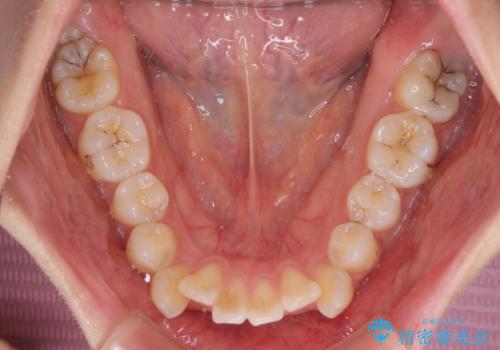

- 前歯のデコボコや口元の突出感、口の閉じにくさを気にして来院された患者様です。

上下左右第一小臼歯4本を抜歯し、ワイヤー装置にてデコボコを解消しながら口元を引っ込めるよう矯正治療を行うこととしました。

抜歯スペースを閉じている過程で、左側の上下犬歯が引っかかってしまい、進捗が停滞しましたが、当初予定の2年~2年半の間で無事に治療を終えることができました。